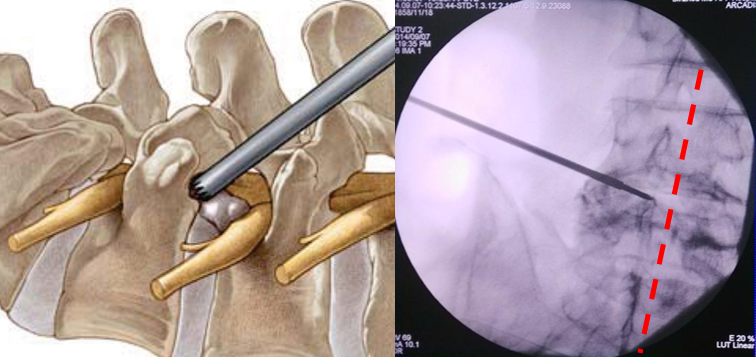

体表定位(用克式针标记进针路线)

椎间盘突出在L2-L3和L3-L4水平,选择在旁开中线10 cm进入。椎间盘突出在L4-L5和L5-S1水平,选择在旁开中线12-14 cm进入。实际的旁开距离还需要依病人的身体大小和肥胖程度作适当调整。肥胖、椎间孔狭小、小关节面假性关节病的病人旁开的距离要大一些。对向下掉的髓核,进入点要偏向头侧和外侧。

体表定位(C型臂下影像)

放置导丝(扩张软组织)用锋利的小手术刀在进针点皮肤切开一个大约8 mm的切口。沿着导丝向小关节方向插入导杆。在导杆外沿着导杆逐级放套管向外扩张软组织。

扩椎间孔骨钻套在套管的外边。沿着套管放置骨钻,去掉小关节远端增生的骨质,扩大椎间孔。

使用骨钻时,用C型臂从前后和侧面确定器械和骨钻顶端的位置。骨钻的最前端不能超过中线,以避免刺激或损伤神经。

放置工作套管(工作通道)独特设计的套管顶端可以保护神经根免遭损伤

用C型臂确定工作套管放置的位置。正确的位置应该是放在神经根下方,椎间盘水平,顶端正好在中线,开口朝向突出的髓核。